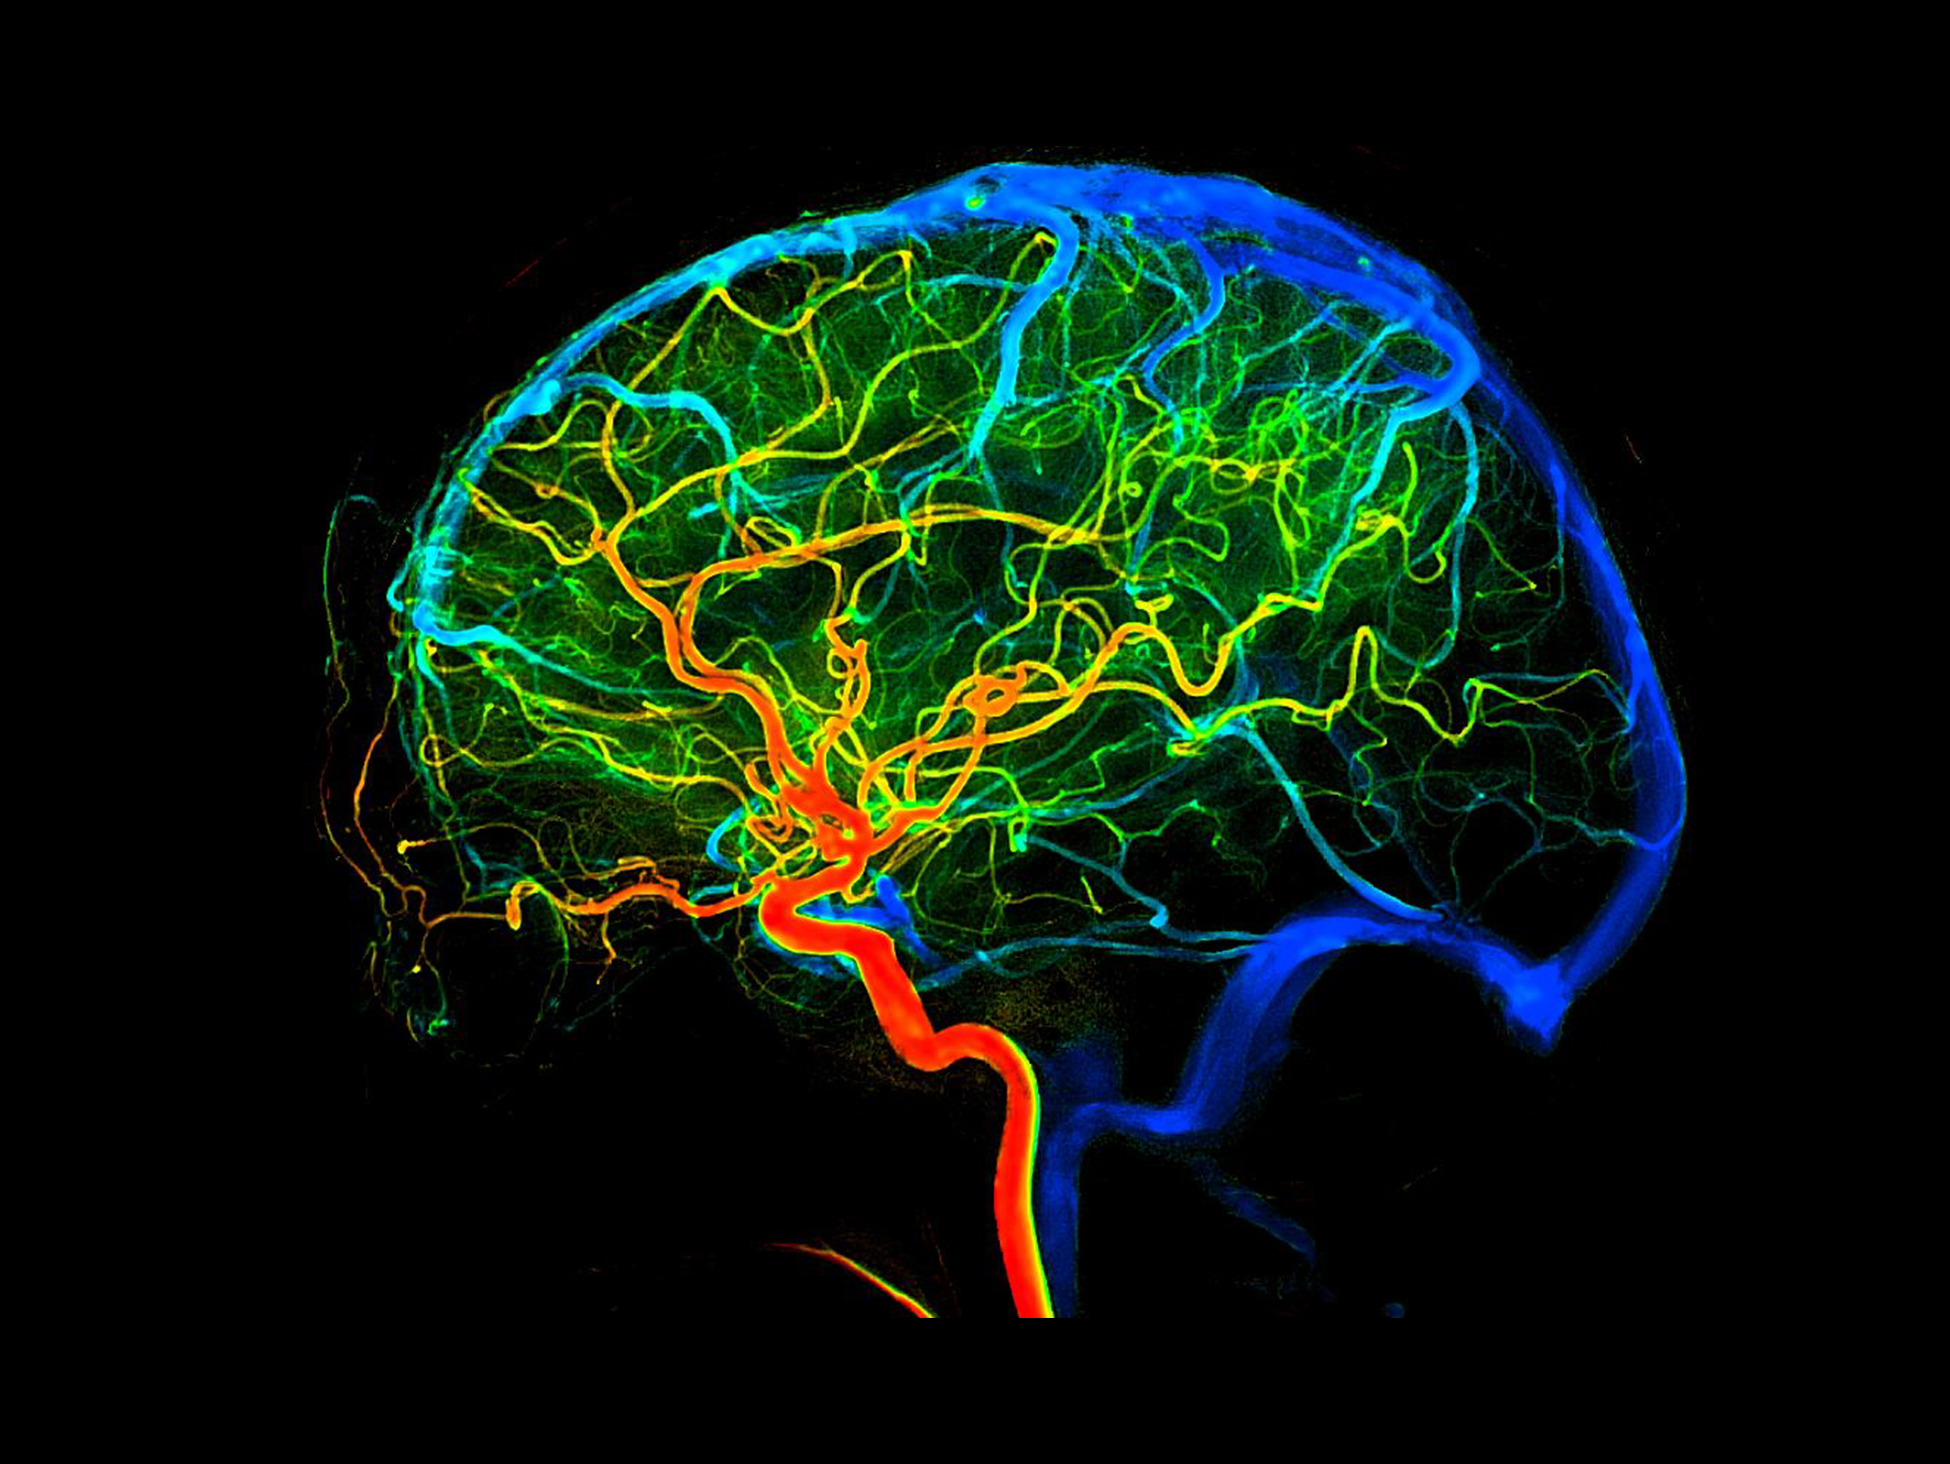

Analiză 2D a fluxului sanguin*

Vizualizează modificările de perfuzie pentru a determina dacă tratamentul poate fi finalizat, oferind variații detaliate ale parametrilor de perfuzie care ajută echipa medicală să evalueze eficiența intervenției.